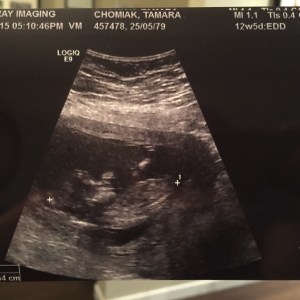

13 week ultrasound: [Oct 2015, already sucking his/her thumb]